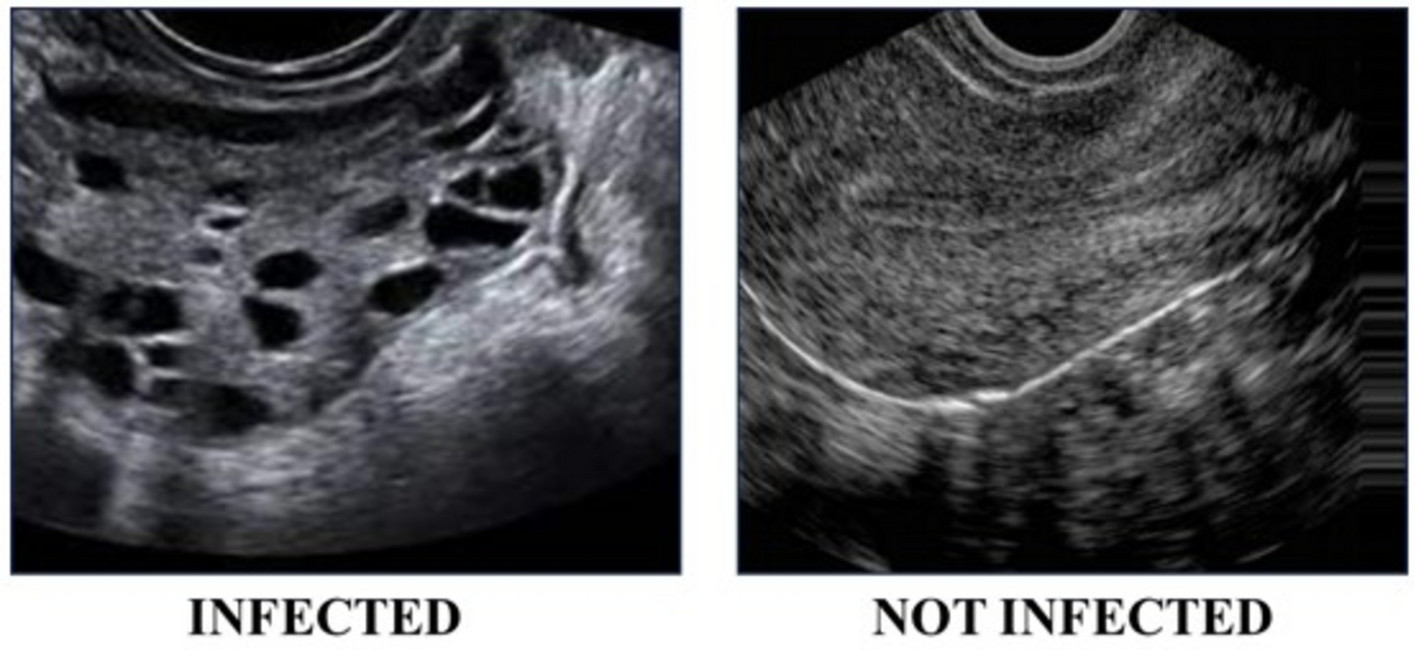

Visual comparison of ultrasound images from patients with and without PCOS.

Figure 2